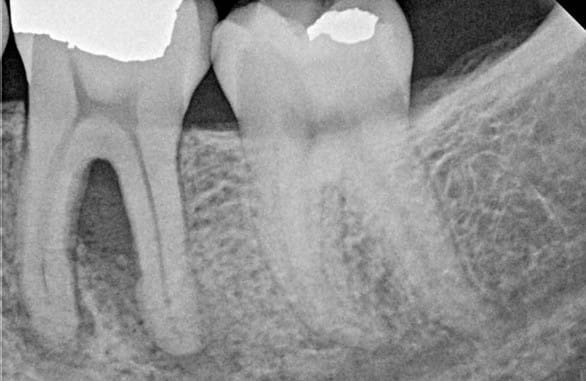

Patient presented on the day of treatment with significant bone loss and infection.